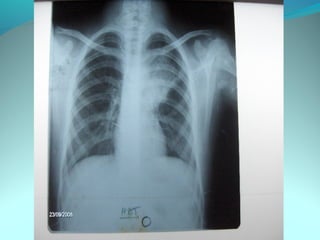

Opacité occupant la partie externe du 1/3 infer du poumon droit

dense et homogene ovalaire de 8cm de grand axe vertical

La limite externe se confend avec une opacité d’environ 1cm comble

les coupole costodiaphragmatique droit

Limitée a sa partie sup par la petit sessure qui est epaisse et pas de

lyse costale

 DIAGNOSTIC :DIAGNOSTIC :

 1_1_cancer bronchique droit( d epaississement)

 2_2_ kyste hydatique au stade sain